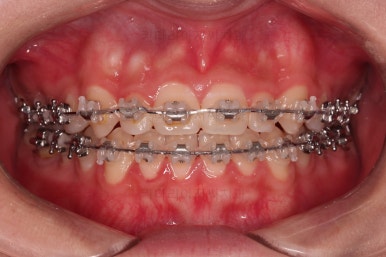

가벼운 철사에서 두꺼운 철사로 주기적으로 바꿔감에 따라 치열이 점점 가지런해지고 있습니다.

현재 모습도 나쁘지 않지만 좀 더 디테일을 맞춰주기 위해서 고무줄도 끼고, 왜소치 때문에 생기는 사이즈 부조화문제로 정중선이 안맞는 점은 일정 부분 수용하면서도 최대한 맞춰보기로 했습니다.

좀 더 디테일을 맞춰주고요.

얼굴모습도 확인하고, 얼굴에서의 치열의 조화도 최종 확인하고 서서히 부산옥니교정 마무리를 합니다.

앞니 각도, 가지런한 느낌, 덧니 등 모든 점이 다 개선되었네요.

입안의 모습에서도 모든게 다 좋아졌고요.

웃는 모습과도 매우 조화롭게 치열이 가지런해졌네요.

앞니 각도가 개선되면서 웃을 때 보이는 치열도 가득차 보이고 환해보이고요.